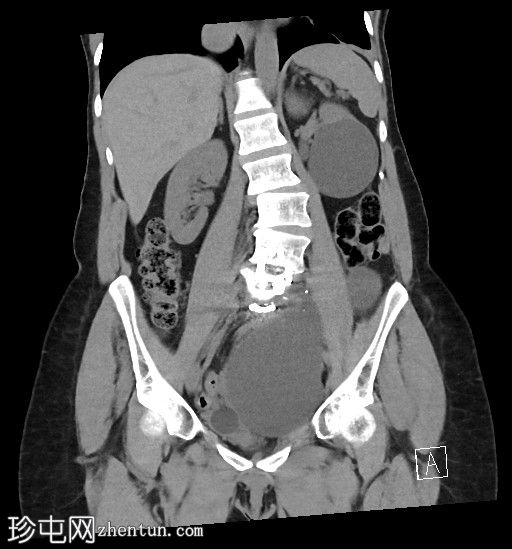

轴位

平扫

左侧腹膜后可见一巨大囊性肿块,位于左侧腰大肌内侧,紧邻多个手术夹(ALIF手术所用),这些手术夹紧贴囊性肿块后壁。

膀胱已行引流管减压,并被囊性肿块向右侧推移。

子宫和左侧附件在囊性肿块前方保持正常的脂肪间隙,因此附件囊性病变的可能性较小。

左侧输尿管难以辨认,因为它位于囊性肿块下缘后方。